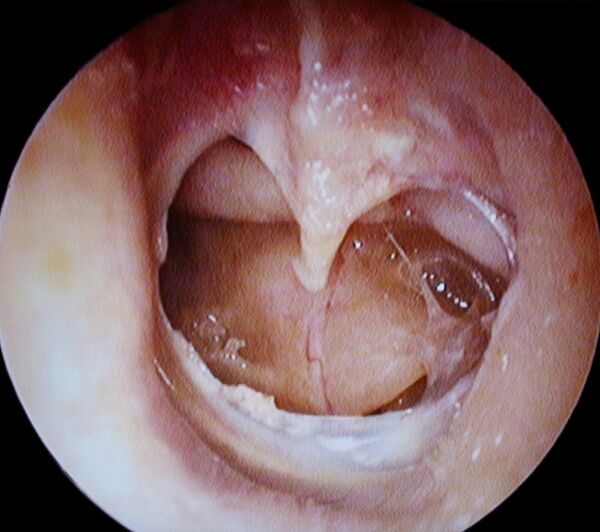

Мирингопластика

Мирингопластика (новолат. myringoplasty) — операция по восстановлению целостности барабанной перепонки.[2]

Метод мирингопластики, позволяющий достичь необходимой герметичности и избежать последующих дегенеративных изменений в трансплантате. Для устранения перфорации, из фасции височной мышцы формируют двойной фасциальный лоскут, размещают его с двух сторон барабанной перепонки.[3]